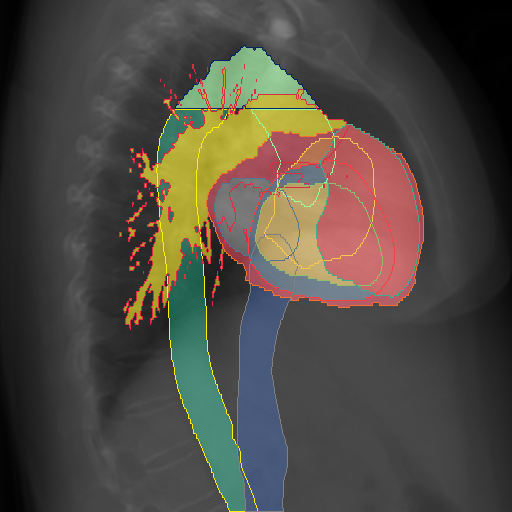

We display qualitative results in Fig. 3. The annotators tend to be content with most annotations. There are edits at the extensions of the esophagus, trachea, and aorta and corrections of the lower ribs. There is little consensus for classes in the abdominal area, such as the stomach, as seen on the right of Fig. 3 . In contrast, the annotators often align for bone classes.

We show the quantitative segmentation performance against medical expert annotations for all classes in Fig. 3 . The dashed lines represent the IAA, whereas the dotted line displays the average MAA. As the task for the human annotators was not to annotate from scratch but to correct wrong pixel-wise predictions, we can see a high MAA for most classes. In the frontal view, the most significant disagreements exist for rare bone structures such as L3 and C4, lower ribs, the mediastinal distribution, or the breast tissue. The IAA and MAA are highly similar with mIoU of respective 95% and 94%. The Hausdorff distance for MAA is slightly lower than the IAA, indicating slight differences in boundary annotations while maintaining a considerable overlap with the other annotator. In the lateral view, the concrete delineation of rib structures appears ambiguous, leading to lower MAA and IAA with a greater IAA than MAA for all metrics in this supercategory. Overall there is less agreement between the medical experts in the lateral view, leading to a better average MAA than IAA across all metrics (i.e. 85% vs 83% mIoU). While the experts propose changes to the original predictions, they are often not overlapping. In the lateral view, rib segmentations can become quite hard to interpret. While both annotators disagree with the rib segmentations, they do not always agree on how they should look. Similarly to the frontal view, tube-like structures like the esophagus are extended as they can appear fractured at times.